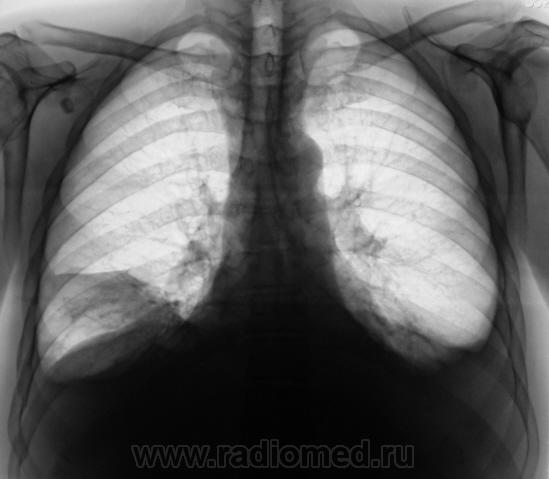

Пациент направлен на исследование с диагнозом "Правостороняя пневмония".

Междолевое осумкование выпота справа. Ну и конечно двустор.свободный.

Явная приподнятость диафрагмы настораживает...

За три дня, следовательно, 0,5 л жидкости слева ушло.....а справа резко прибыло ...как будто только диафрагмы, но без значительного прибавления жидкости...Интересно....печень же за три дня так не увеличиться...

Поскольку такой внезапный парез диафрагмы маловероятен...смею предположить наличие базального плеврита справа...он же - диафрагмальный плеврит. Здорово бы было посмотреть на УЗИ - за три секунды решили бы проблему.